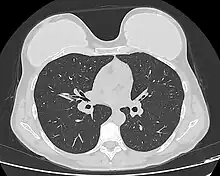

Computed tomography of a woman with breast implants

Breast MRI of a patient with implant (blue)

The breast implant has no clinical bearing upon lumpectomy breast-conservation surgery for women who developed breast cancer after the implantation procedure, nor does the breast implant interfere with external beam radiation treatments (XRT); moreover, the post-treatment incidence of breast-tissue fibrosis is common, and thus a consequent increased rate of capsular contracture.[122] There is tentative evidence that women who have had breast augmentation, have worse breast cancer prognosis.[123] The use of implants for breast reconstruction after breast cancer mastectomy appears to have no negative effect upon cancer-related death.[119][124]